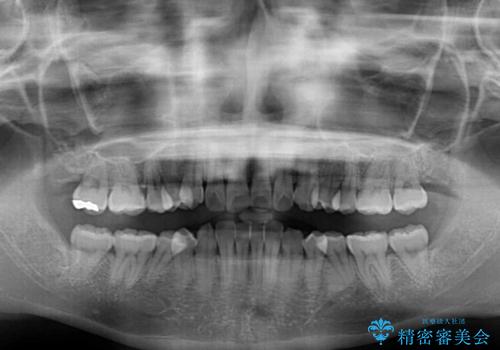

- 前歯のデコボコと強い咬みしめを気にして来院された患者様です。

インビザラインを用いて、前歯の叢生を解消するとともに、ディープバイトを改善していくこととしました。